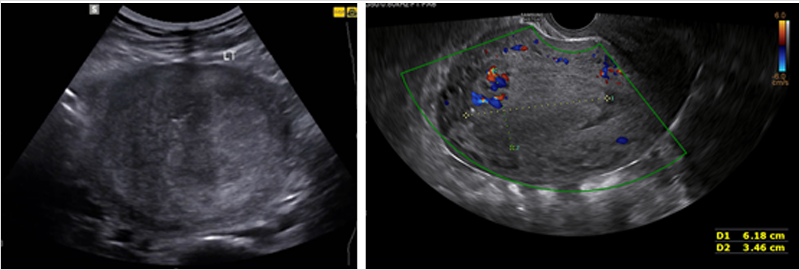

그림4. 잔류태반. (좌) 자궁강 내에 에코성 덩이가 관찰됨, (우)자궁내막, 자궁근층에 혈류가 증가되어 있음.

잔류태반초음파에서 자궁강내에 에코성 비균질한 덩이가 관찰되며, 자궁내막이나 자궁근층에 혈류가 증가되어 보이기도 한다.